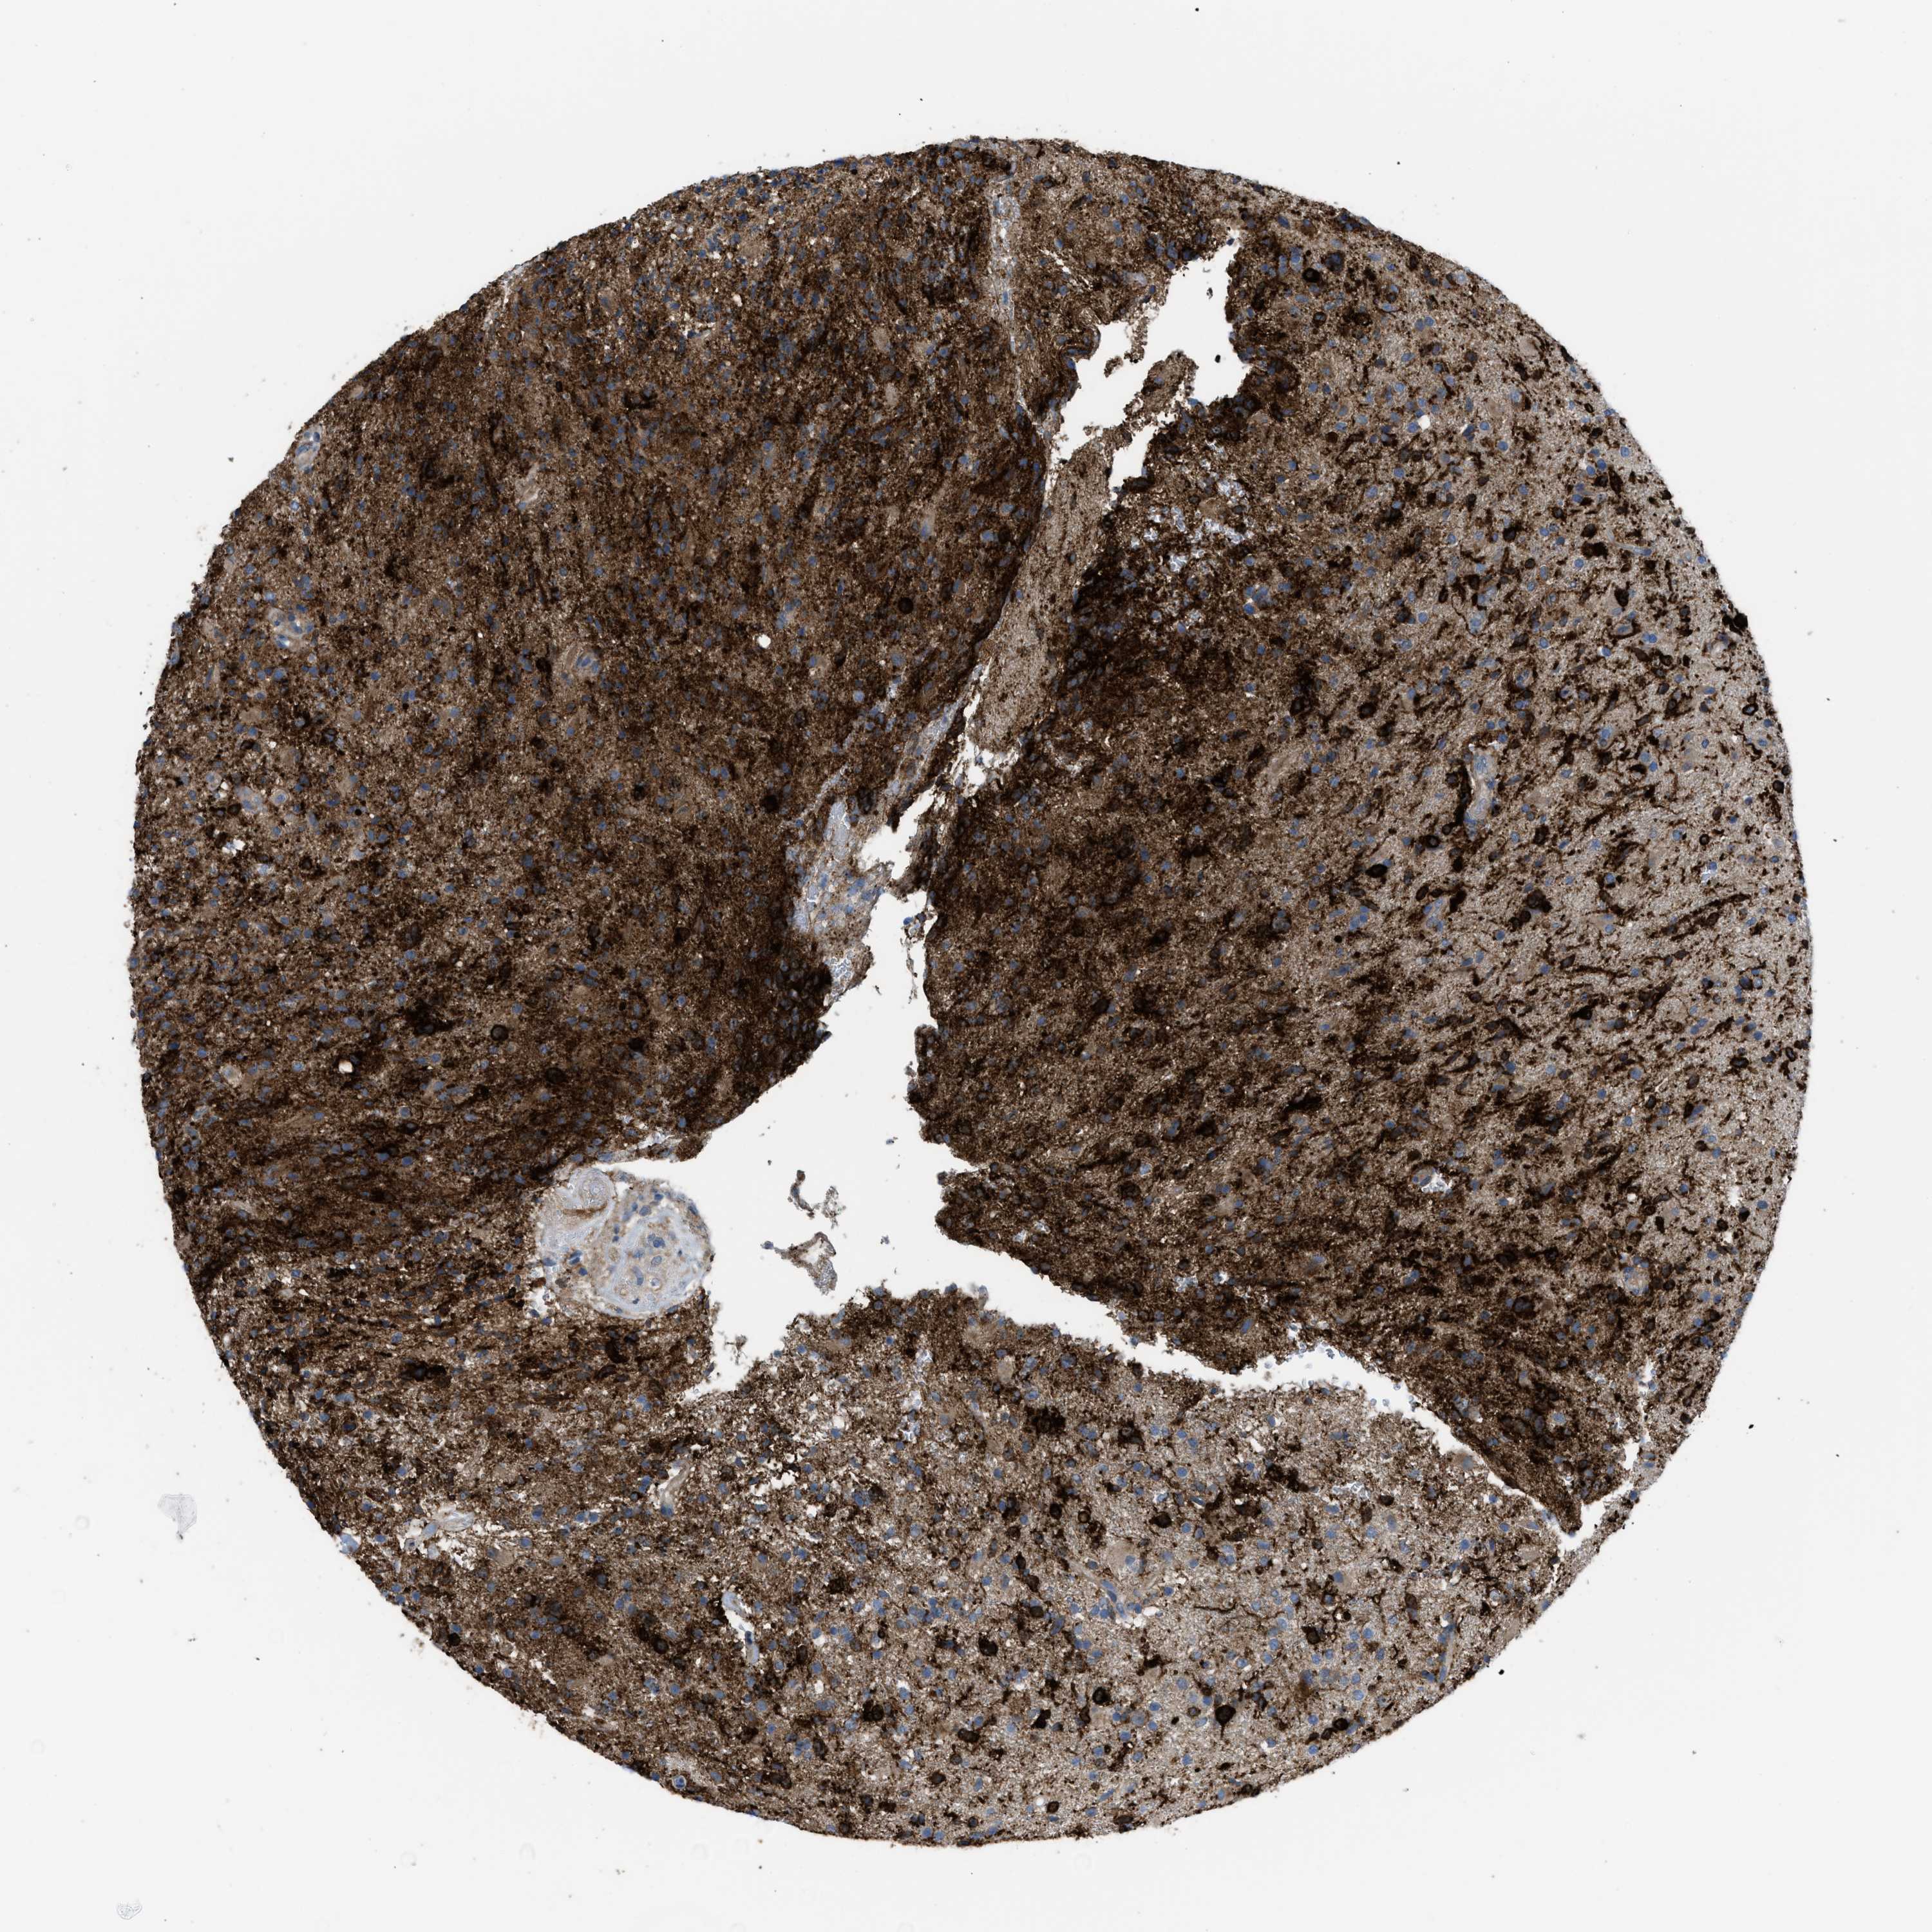

GLIOMA - Protein expressioni

A mouse-over function shows sample information and annotation data. Click on an image to view it in a full screen mode. Samples can be filtered based on level of antibody staining by selecting one or several of the following categories: high, medium, low and not detected. The assay and annotation is described here.

Note that samples used for immunohistochemistry by the Human Protein Atlas do not correspond to samples in the TCGA dataset.

Antibody stainingi

Antibody staining in the annotated cell types in the current human tissue is reported as not detected, low, medium, or high, based on conventional immunohistochemistry profiling in selected tissues. This score is based on the combination of the staining intensity and fraction of stained cells.

Each image is clickable and will lead to virtual microscopy that enables deeper exploration of all samples and also displays staining intensity scores, fraction scores and subcellular localization as well as patient and tissue information for each sample.

Glioma, malignant, High grade

Glioma, malignant, Low grade

Glioma, malignant, NOS